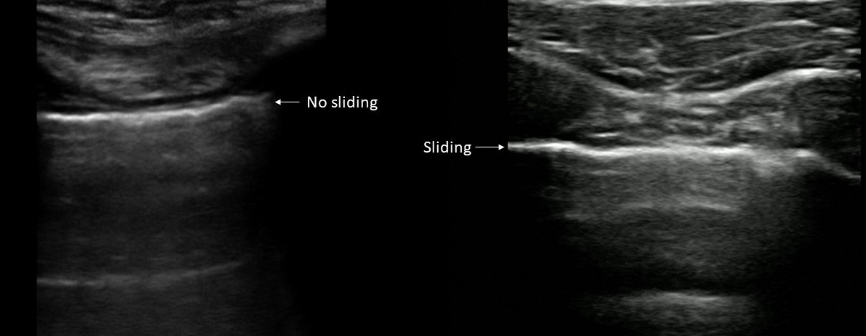

Transverse and longitudinal views of the suprapubic region, commonly referred to as the suprapubic view, are explored for free fluid. The bladder and rectouterina, also known as the rectrovesical pouch or the Douglas pouch, are depicted in this region, which is the most reliant peritoneal space in the supine trauma patient utilizing the bladder as a sonographic window in a transverse sweep. The probe would be positioned longitudinally along the midclavicular line at the third or fourth intercostal space in bilateral thoracic images A traumatic pneumothorax can be detected by lung sliding, which is a sensitive but non-specific indication.

The different angles from which the FAST scans were conducted while all patients were lying in supine position on the examination couch, and three points on the lung were inspected (the upper anterior point, the lower anterior point and the posterior lateral alveolar or pleural point) on each side. The abdomen was examined in three points as well. The longitudinal view of the RUQ, LUQ, showed the most dependent peritoneal space in the supine trauma patient to depict the urinary bladder and rectouterina, or rectrovesical pouch, or the pouch of Douglas and subxiphoid space. The results clearly show that the greatest percentage of FAST scans performed (n=26) revealed no free fluid (86.6%). This was followed by splenorenal views (n=2) 6.6%, hepatorenal views (n=1) 3.3%, and pelvic views (n=1) 3.3%. FAST scans on the lungs revealed pneumothorax in (n=13) 43.33% of the patients. FAST scan with pneumothorax finding is presented in Figure 1. The participants’ various organs were impacted overall by blunt injuries. The average time of the examination was 5±3.5 min. The findings showed that the following FAST scan values were attained, with a high 94.4% sensitivity. The results showed that the specificity was 85.71%, the positive predictive likelihood ratio 6.61 or positive predictive value of 3.21% and the negative likelihood ratio 0.06 or negative predictive value of 99.97%. There was not any complication to report in the exanimated cohort.

Figure 1. Thoracic views of FAST.